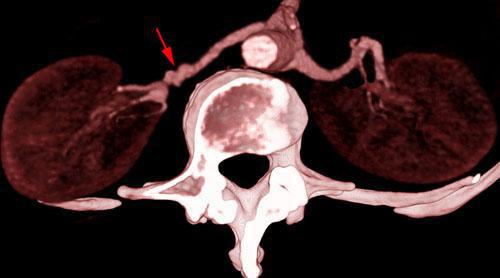

Los estrechamientos focales o segmentarios de la arterias renales son la causa mas frecuente de hipertensión arterial secundaria a enfermedad ateroseclerótica o a displasia fibromuscular.

El estudio puede hacerse mediante Ecografía, Angio RM y AngioTC siendo este último un excelente método de despistaje de esta patología tanto por su disponibilidad actual como por las excelentes imágenes volumétricas que proporciona.